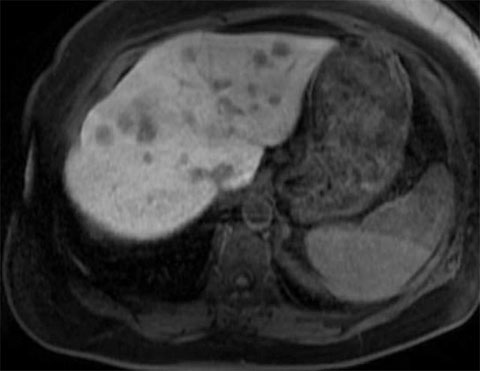

Pre-treatment MRIs

The patient responded well to chemotherapy; in a six-month period from December 2021 to May 2022, there was a significant interval decrease in the size of multiple hepatic metastatic lesions. The patient had approximately 22 peripherally enhancing liver metastases.

We identified 12 total lesions on the patient’s liver; five of these were in segment 2, one was in segment 1, four were in segment 3 and two were in segment 4A.